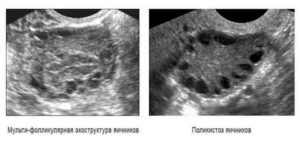

Мультифолликулярность и поликистозность на узи

Мультифолликулярная структура яичников

Мультифолликулярная структура яичников подразумевает 12 созревших фолликулов вместо допустимых 7, что очевидно на снимке УЗИ. Симптомы такой патологии, как правило, отсутствуют, а открывается проблема при прохождении полной компьютерной диагностики для определения причины отсутствия беременности.

Мультифолликулярные яичники и поликистоз в чем разница

Поликистозом называют заболевание, при котором в яичнике образуется множество кист – полостей, заполненных жидкостью. Это опасное патологическое состояние, поэтому врач должен проявлять бдительность, чтобы не спутать мультифолликулярные яичники и поликистоз.

Поликистоз имеет отличительные черты:

- Количество пузырьков превышает 10;

- Их диаметр может достигать 10 мм;

- Кисты чаще располагаются на периферии органа;

- Они имеют плотную капсулу;

- Чаще в патологический процесс вовлекаются оба яичника;

- Отмечается значительное увеличение их в размере.

- Размер яичников – у мультифолликулярных яичников объем немного больше, чем обычно. Длина фолликула при СПКЯ составляет более 40 мм, с нормой 34-37 мм.

- Фолликулы – в обоих случаях наблюдаются множественные структурные элементы. С МФЯ их диаметр составляет не более 9 мм, а при СПКЯ они значительно превышают норму. Капсула фолликула при поликистозе сильно утолщена, что препятствует выходу яйца и провоцирует рост фолликулярных кист.